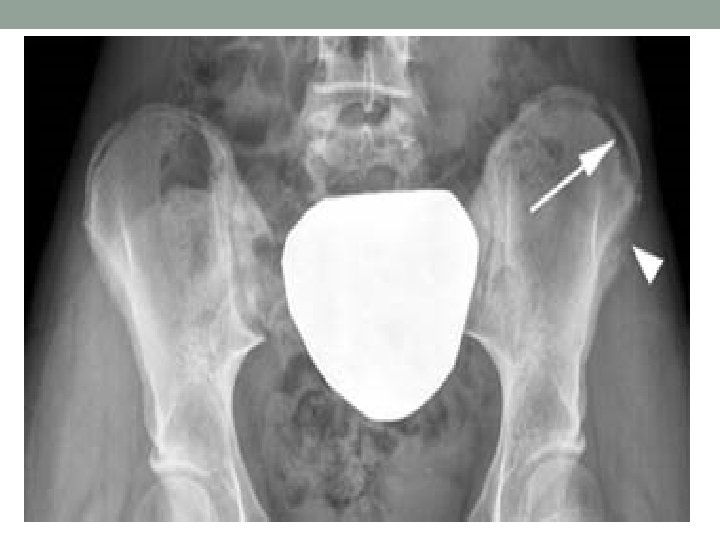

Axillary Vein Thrombosis “effort thrombosis” • Paget-von Schrotter Syndrome • Compression • Costoclavicular Space • Clavicle & 1 st rib • Subclavian Muscle & 1 st rib • Presentation-fatigue & heaviness • Physical Exam • Superficial veins prominent • Venography • Rest and Anticoagulation